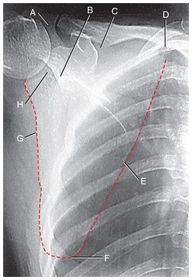

A. acromion B. acromioclavicular joint (AC) C. acromial extremity D. clavicular body E. sternal extremity F. sternoclavicular joint (SC) G. jugular notch H. manubrium of sternum